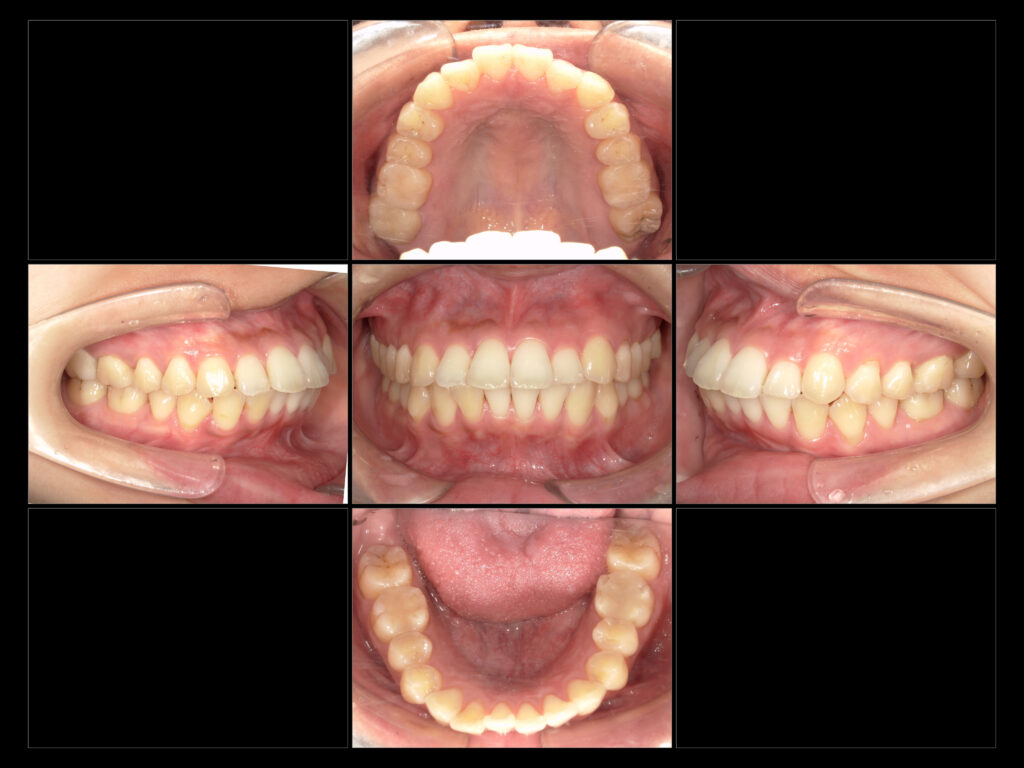

下:治療後口腔内写真

治療内容

e-max In→右上6、右下6、左上6

e-max On →左下6

e-maxCr→右上7

治療期間

費用

来院回数

今回は補綴治療を終えた患者様の症例写真です。

を目的に補綴物のやり替えなど全顎的に根本治療を行いました。

現在は、メンテナンスに通っていただきながら経過観察を追っていきます。